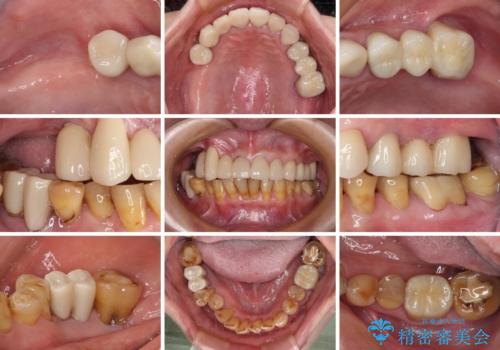

治療途中で放置してしまった前歯 オールセラミッククラウンによる補綴治療

前歯部については抜歯が必要な歯を抜歯し、インプラントやブリッジなどにより補綴治療を行うこととしました。

臼歯部は今後抜歯が必要となった際に、インプラントにより咬合を構築していくこととしました。今回の治療においても、今後の臼歯部の治療に対応できるよう治療計画を立案しています。